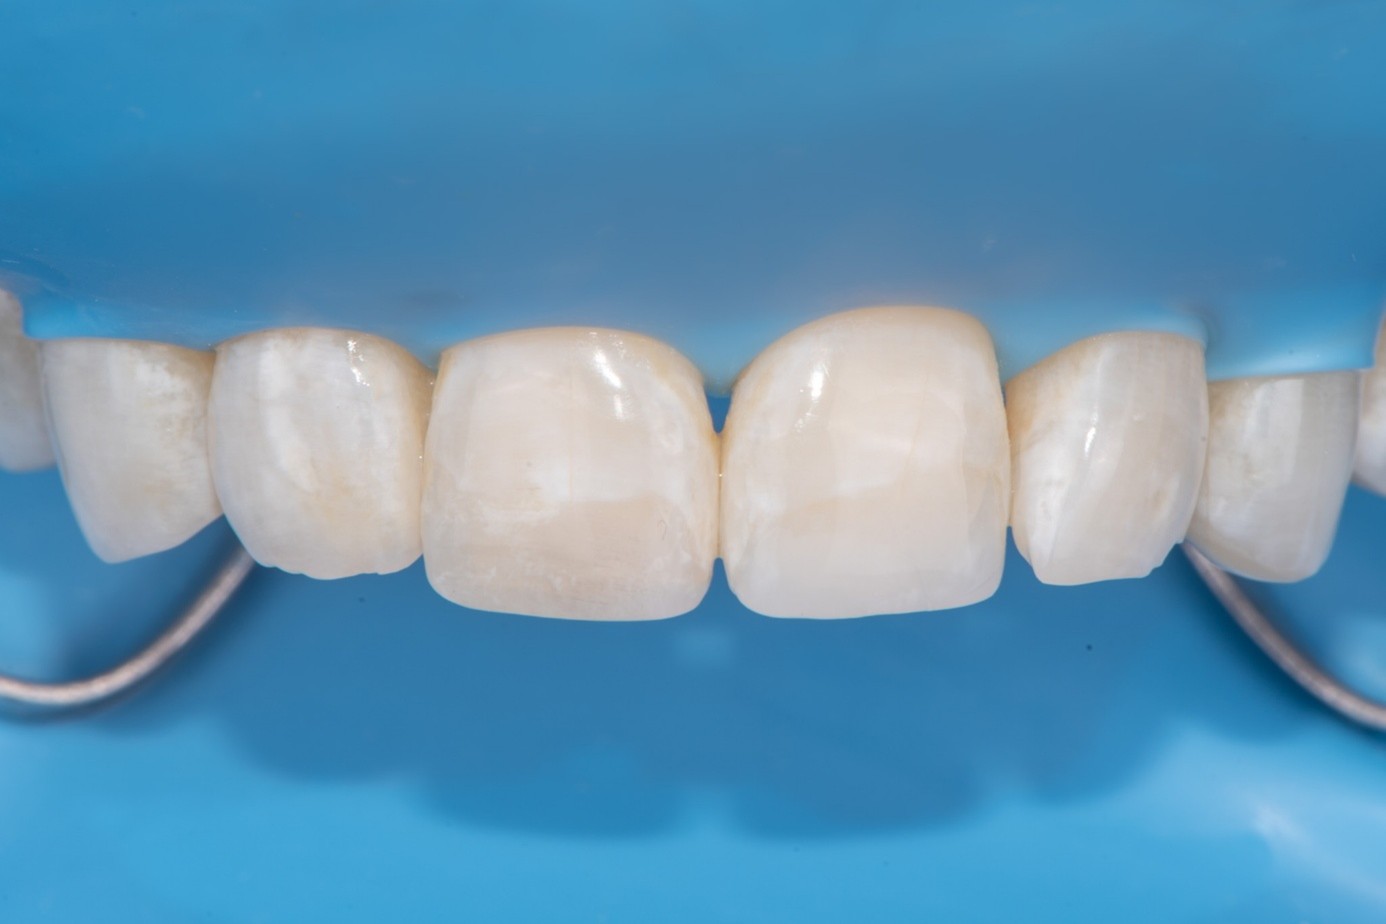

Case 2: Composite Facing Fracture

This case involved a patient with generalized mild anterior wear and an existing composite restoration on the maxillary left central incisor. The restoration extended from the middle third to the incisal edge and had excellent shade match and no marginal discoloration. The patient presented with a fractured central mesial portion of the composite (Figure 14 through Figure 16). Examination revealed a mixed failure pattern: Some adhesive and composite remnants remained on the tooth surface, while the fractured piece showed no residue internally. This finding suggested that the weak point was at the interface between composite and adhesive layer, with a minor cohesive component within the composite itself (Figure 17).

From a clinical standpoint, this pattern is reassuring, as it indicates a strong bond to the tooth substrate and that the restoration had functioned successfully until the composite material itself reached its fracture threshold. Considering the generalized wear pattern and patient history, parafunctional habits were suspected as the main cause of failure—the composite likely fractured when the applied functional stress exceeded its material strength.

Clinical Procedure

After achieving rubber dam isolation, the fractured composite segment was first air-abraded with aluminum oxide particles to clean and roughen the surface. It was then etched with phosphoric acid for 60 seconds, rinsed, dried, and treated with silane to enhance chemical adhesion (Figure 18 through Figure 20).8,9

The tooth surface was similarly air-abraded to remove biofilm and aged resin remnants, then selectively etched with phosphoric acid. Silane was applied intraorally to the exposed composite surface to promote bonding between the old and new composite layers.10 Following this, a universal bonding agent was applied to both the tooth surface and the fractured composite segment (Figure 21 through Figure 24).

Before light-curing, flowable composite resin was placed in the cavity, and the fractured segment was repositioned precisely into its original location. Heated packable composite was avoided due to thinness and brittleness of the fractured piece. Excess bonding and composite were carefully removed using a microbrush. The restoration was then polymerized from multiple directions to ensure optimal cure (Figure 25 and Figure 26). Finally, the restoration was polished and contoured to blend seamlessly with the surrounding tooth structure and adjacent composite (Figure 27).

The result was a seamless repair, preserving sound tooth structure and maintaining the excellent esthetic integration of the original restoration.

(14.) Intraoral view showing the fractured ceramic fragment positioned in place. The piece fits well, although minor gaps are present between the margins due to slight material loss, which can be restored using luting composite.

Figure 14

(15.) Intraoral view showing the fractured ceramic fragment positioned in place. The piece fits well, although minor gaps are present between the margins due to slight material loss, which can be restored using luting composite.

Figure 15

(16.) Intraoral view showing the fractured ceramic fragment positioned in place. The piece fits well, although minor gaps are present between the margins due to slight material loss, which can be restored using luting composite.

Figure 16

(17.) Mixed cohesive failure of the restoration, with a very small amount of adhesive remaining on the fragment, while the majority of the fractured surface shows fresh composite, indicating cohesive failure within the material.

Figure 17

(21.) Intraoral view after rubber dam isolation, showing prepared surfaces: both sandblasted and etched, with silanization applied only to the composite surface, ready for reattachment.

Figure 21

(22.) Intraoral view after rubber dam isolation, showing prepared surfaces: both sandblasted and etched, with silanization applied only to the composite surface, ready for reattachment.

Figure 22

(23.) Intraoral view after rubber dam isolation, showing prepared surfaces: both sandblasted and etched, with silanization applied only to the composite surface, ready for reattachment.

Figure 23

(24.) Intraoral view after rubber dam isolation, showing prepared surfaces: both sandblasted and etched, with silanization applied only to the composite surface, ready for reattachment.

Figure 24

(27.) Final intraoral view after complete polymerization under glycerin gel, showing a seamless repair with invisible margins, making the fracture line undetectable.

Figure 27